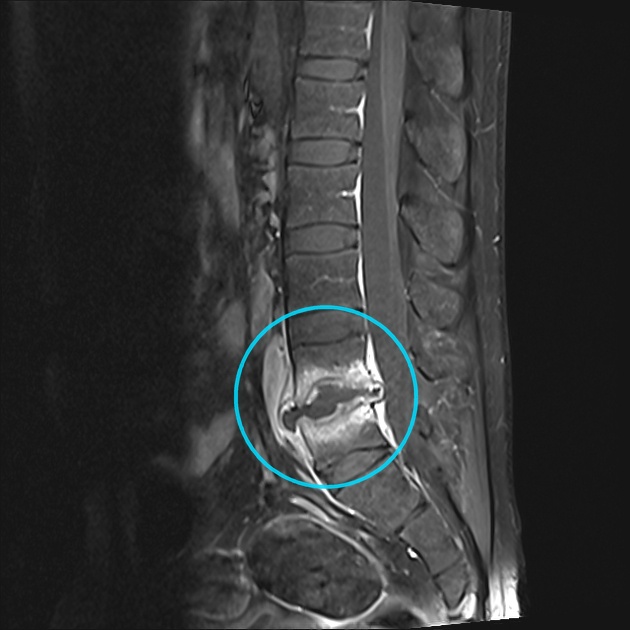

What's the Diagnosis?